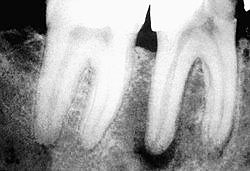

Рентгенологические снимки хорошо запломбированных корневых каналов.